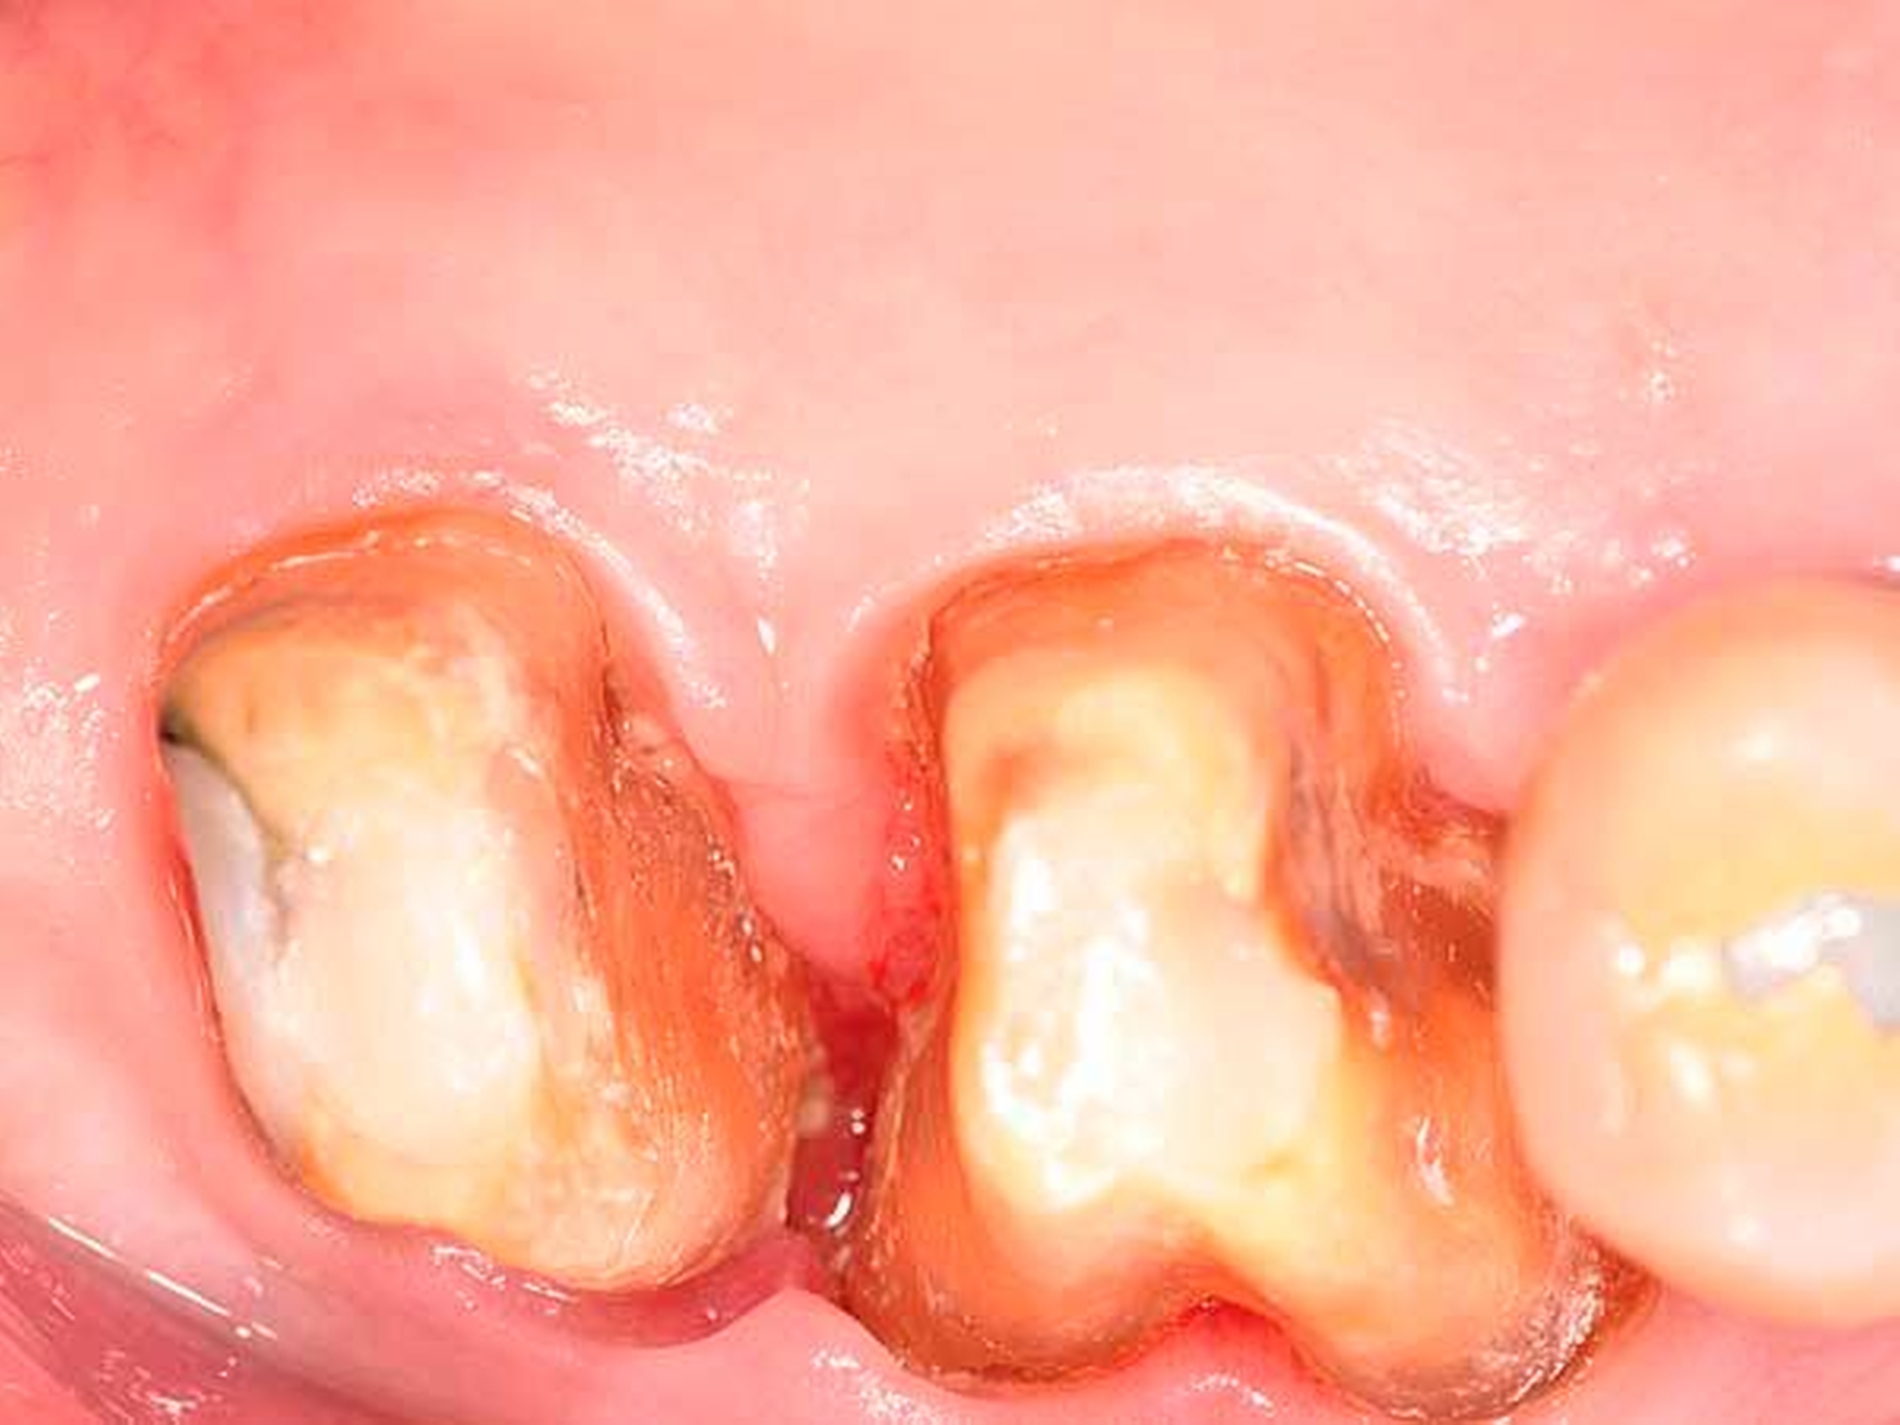

Molaren mit fortgeschrittenem Furkationsbefall weisen gegenüber anderen Zahntypen sowie gegenüber nicht furkationsbefallenen Molaren deutlich erhöhte Misserfolgs- und schlussendlich auch Zahnverlustraten auf [Nibali et al., 2016]. Dies ist auf die schlechte Zugänglichkeit der Furkationsregion für die Biofilmkontrolle zurückzuführen (siehe auch Abbildung 8a). Eine nicht-chirurgische Therapie, auch in Kombination mit Adjuvantien wie einem lokalen Antibiotikum [Dannewitz et al., 2009], oder eine chirurgische Therapie mittels Accessflaps [Graziani et al., 2015] sind zur Resolution einer Furkationsbeteiligung nicht geeignet.